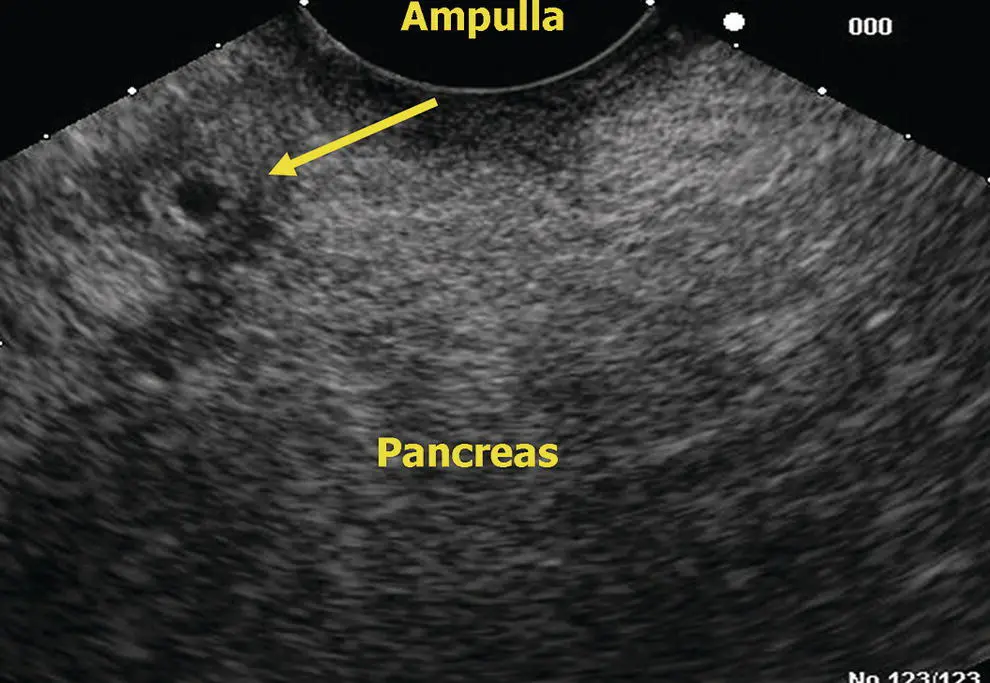

Figure 6.13 Linear EUS: ampulla.